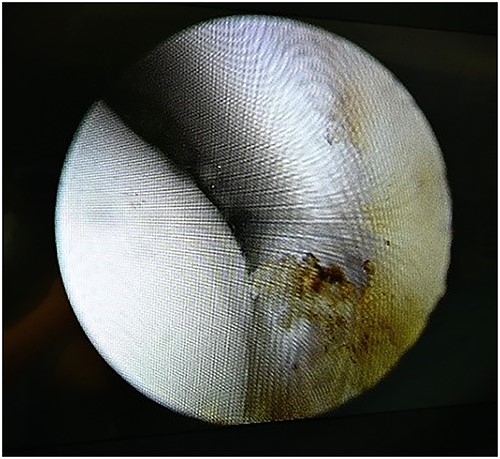

A 28-year-old male patient presented with a history of ankle pain and difficulty with weight-bearing activities on the right side. Radiographic evaluation revealed a large osteochondral defect in the talus. (Figs 1–3).

The patient underwent ankle arthroscopy (Fig. 4), mini open debridement of the affected area (Figs 5 and 6), followed by intra-articular injection of BMC derived from his own bone marrow. (Figs 7 and 8).